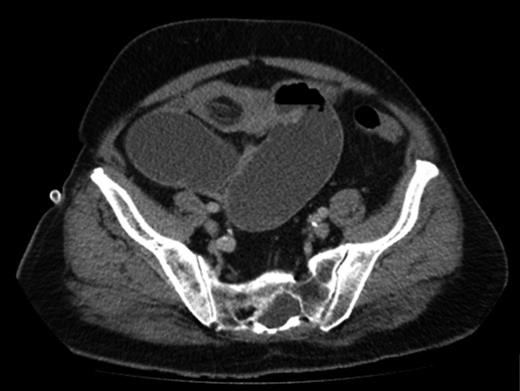

An abdominal X-ray confirmed SBO (Fig. 1). In view of having a virgin abdomen, a CT scan was arranged. This revealed SBO secondary to a mass in the small bowel, causing an ileojejunal intussusception (Fig. 2).